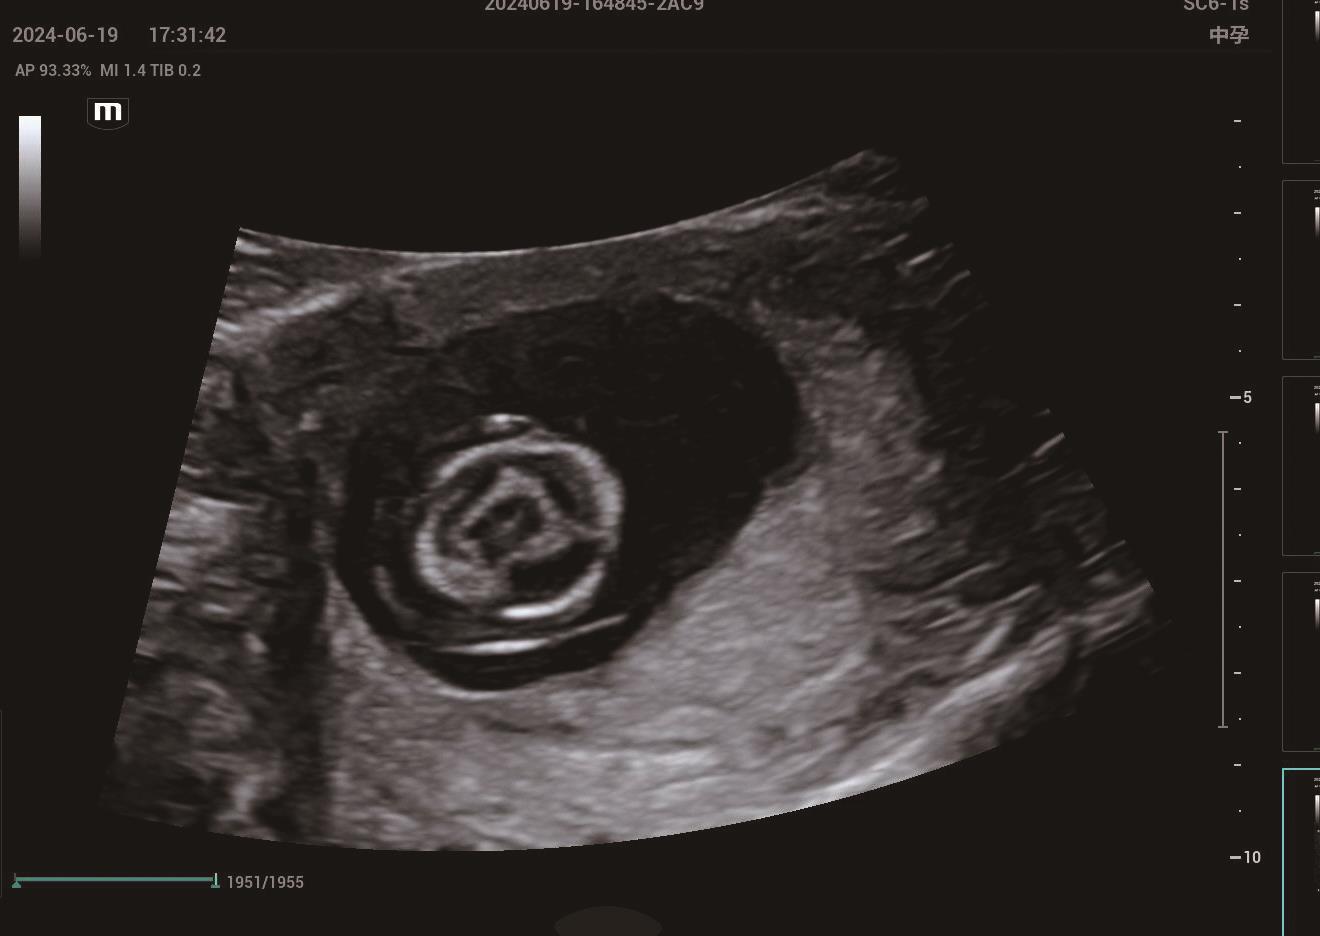

• 四维超声联合母体血清妊娠相关血浆蛋白A水平对孕中期胎儿中枢神经系统畸形的诊断价值

2025, 35(18):72-76. DOI: 10.3969/j.issn.1005-8982.2025.18.012

摘要 (152) HTML (24) PDF 964.26 K (89) 评论 (0) 收藏

摘要:目的 探讨四维超声联合母体血清妊娠相关血浆蛋白A(PAPP-A)水平对孕中期胎儿中枢神经系统(CNS)畸形的诊断价值。方法 选取2022年10月—2024年10月新疆军区总医院接收的187例孕妇,年龄20~40岁,孕周20~26周;根据出生后的评估结果,对胎儿CNS畸形进行统计,根据胎儿是否发生CNS畸形将孕妇分为畸形组(10例)与非畸形组(177例),比较两组四维超声检查结果及母体血清PAPP-A水平,并采用受试者工作特征(ROC)曲线分析四维超声联合PAPP-A水平对孕中期胎儿CNS畸形的诊断效能。结果 四维超声诊断孕中期胎儿CNS畸形的敏感性为80.00%(95% CI:44.4,97.5),特异性为87.57%(95% CI:81.8,92.0)。畸形组母体血清PAPP-A水平低非畸形组(P <0.05)。ROC曲线结果显示,四维超声联合血清PAPP-A水平诊断孕中期胎儿CNS畸形的敏感性为90.0%(95% CI:0.555,0.997),特异性为97.2%(95% CI:0.935,0.991),曲线下面积为0.954(95% CI:0.879,1.000)。结论 四维超声与母体血清PAPP-A水平联合检测在诊断孕中期胎儿CNS畸形方面显示出高敏感性和特异性,其为孕中期胎儿CNS畸形的有效诊断手段。